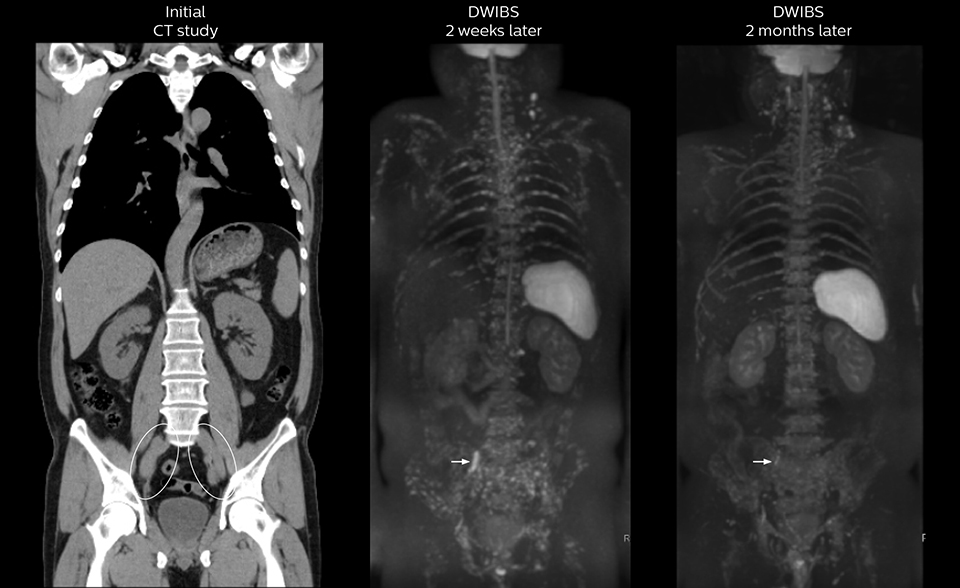

“The DWIBS sequence’s value in oncology cases is due to the high contrast it creates between lesions and surrounding tissue. Whole body DWI is requested by physicians who need to clarify TNM staging or determine therapeutic strategies, oncologists in need of diagnosis or follow-up scans, surgeons who need to see the presence of distant lesions that are sometimes difficult to detect by CT before surgery, and urologists for the evaluation of bone lesions, and the effect of chemotherapy and radiotherapy.”

After implementing the improved whole body protocol, the radiology team initially did not see a large increase in referrals, although Dr. Nobusawa saw clinical cases where the DWIBS images provided him valuable information for diagnosis. This is why Dr. Nobusawa and Mr. Naka started to actively educate referring physicians about the value of whole body DWIBS. They organized several presentations for physicians in the hospital, where they explained how DWIBS can be of value in oncology patients. The information it provides can be useful for physicians when staging cancer, as well as when determining or adjusting treatment strategy. Mr. Naka remembers some cases where DWIBS provided remarkable information. “In one example, DWIBS visualized bone lesions that could not be seen on PET or SPECT. In another case we had found a bone lesion when a normal L-spine scan for narrowing of the disk space was done. One extra DWIBS scan (2 stations, 8 minutes) demonstrated a lesion that later was confirmed to be the primary region of cancer.”